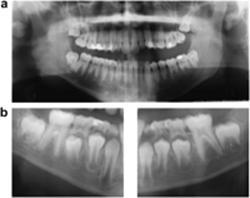

Panoramic radiographs of 12 children (7 boys and 5 girls) aged 6 years 4 months to 8 years 9 months with unexpected early apical resorption of primary teeth were identified from a dental archive of 588 patients. After written request, follow-up radiographs were obtained (2–15 year interval between early and follow-up radiographs). The radiographs were examined in order to verify the abnormal resorption pattern of the primary teeth and dental deviations in the permanent teeth, known to predispose for root resorption (i.e. invaginations, narrow crowns, abrupt root deflections, slender roots, short roots, taurodontia, agenesis, deviant pattern of eruption).

Dental pantomograms of the early mixed dentitions for evaluating mainly the primary dentition

Two phenotypically different groups of resorption were identified according toBille et al. (2007). Eight children (four boys and four girls) belonged to group I (Figure 1) and four children (three boys and one girl) to group II (Figure 2).

Figure 1

Dental pantomogram of a girl aged 6 years 4 months in the early mixed dentition with unexpected early apical resorption. Invaginations of the permanent maxillary lateral incisors, short roots of the permanent maxillary central incisors, and agenesis of the left permanent mandibular second premolar are seen. A follow-up radiograph (not shown) taken 2 years 8 months later confirmed findings of dental deviations seen on the first radiograph, but did not provide any additional findings of dental deviations in the permanent dentition.

View larger version:

Figure 2

Dental pantomogram of a boy aged 8 years 9 months in the early mixed dentition with unexpected early apical resorption of the entire root complex and partial resorption of the crown of the primary maxillary second molars. Taurodontia is seen in the permanent maxillary first molars and agenesis of all second premolars. A follow-up radiograph (not shown) taken 3 years 8 months later confirmed the findings of dental deviations seen in the first radiograph. Additionally, the mandibular first premolars showed a deviant eruption pattern with resorption of the primary mandibular second molars.

The following morphological characteristics and dental anomalies were seen in the subjects: invaginations in five (Figure 1), a narrow crown of the maxillary central or lateral incisors in one (not shown), abrupt root deflection of a maxillary incisor in one (Figure 3), slender or tapered roots in six (Figure 3), short roots in three (Figures 1 and 3), taurodontia in six (Figures 2 and 3), and agenesis in three (Figures 1 and 2). Pipette-shaped teeth were not registered.

Figure 3

(a) Follow-up radiograph of the permanent dentition in a girl aged 11 years 6 months. Abrupt root deflection of the left maxillary central incisor, slender roots of the mandibular first molars, short roots of the second premolars and mandibular incisors, and taurodontia of the second molars. A deviant resorption pattern of the right primary maxillary second molar is seen. Dental pantomogram (DPT; not shown) of the early mixed dentition showed unexpected early apical resorption of the primary teeth. (b) Enlargement of the DPT of the girl shown in (a). Abrupt root deflection of the left maxillary central incisor is seen in (c). Enlargement of the right mandibular region of the DPT showing taurodontia of the second molar, slender roots of the first molar, and a short root of the second premolar.

Figure 4

(a) Dental pantomogram (DPT) of the permanent mandibular regions of a girl aged 15 years 11 months showing short roots of the permanent mandibular first molars. The girl had not received orthodontic treatment. (b) For comparison of the mandibular regions (shown in (a)), two segments of the DPT of the early mixed dentition taken 9 years 5 months earlier of the same girl are shown. The root length of the first permanent molar appears longer than shown in (a), and accordingly an unexpected root resorption of the permanent mandibular molars has occurred. Unexpected early apical resorption of primary mandibular molars is also seen in (b).

Figure 5

(a) Dental pantomogram (DPT) of the permanent dentition of a boy aged 17 years 5 months with invaginations of the lateral incisors and short roots of mandibular molars. (b) For comparison of the mandibular regions (shown in (a)), two segments of a DPT of the same boy taken 9 years 3 months earlier are shown. Root resorption of the permanent mandibular molars has occurred since the DPT shown in (a) was taken. The patient has received orthodontic treatment. Note less severe early apical resorption of the primary teeth.